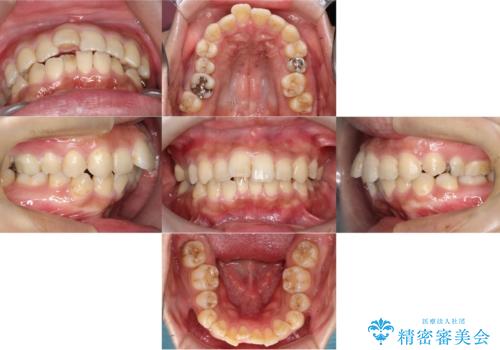

[ 非抜歯矯正 ] 歯を抜かずに出っ歯の治療

![[ 非抜歯矯正 ] 歯を抜かずに出っ歯の治療の症例 治療後](https://seimitsushinbi.jp/wp/wp-content/uploads/2025/03/IMG_7513-500x350.jpg?v=1741945816)